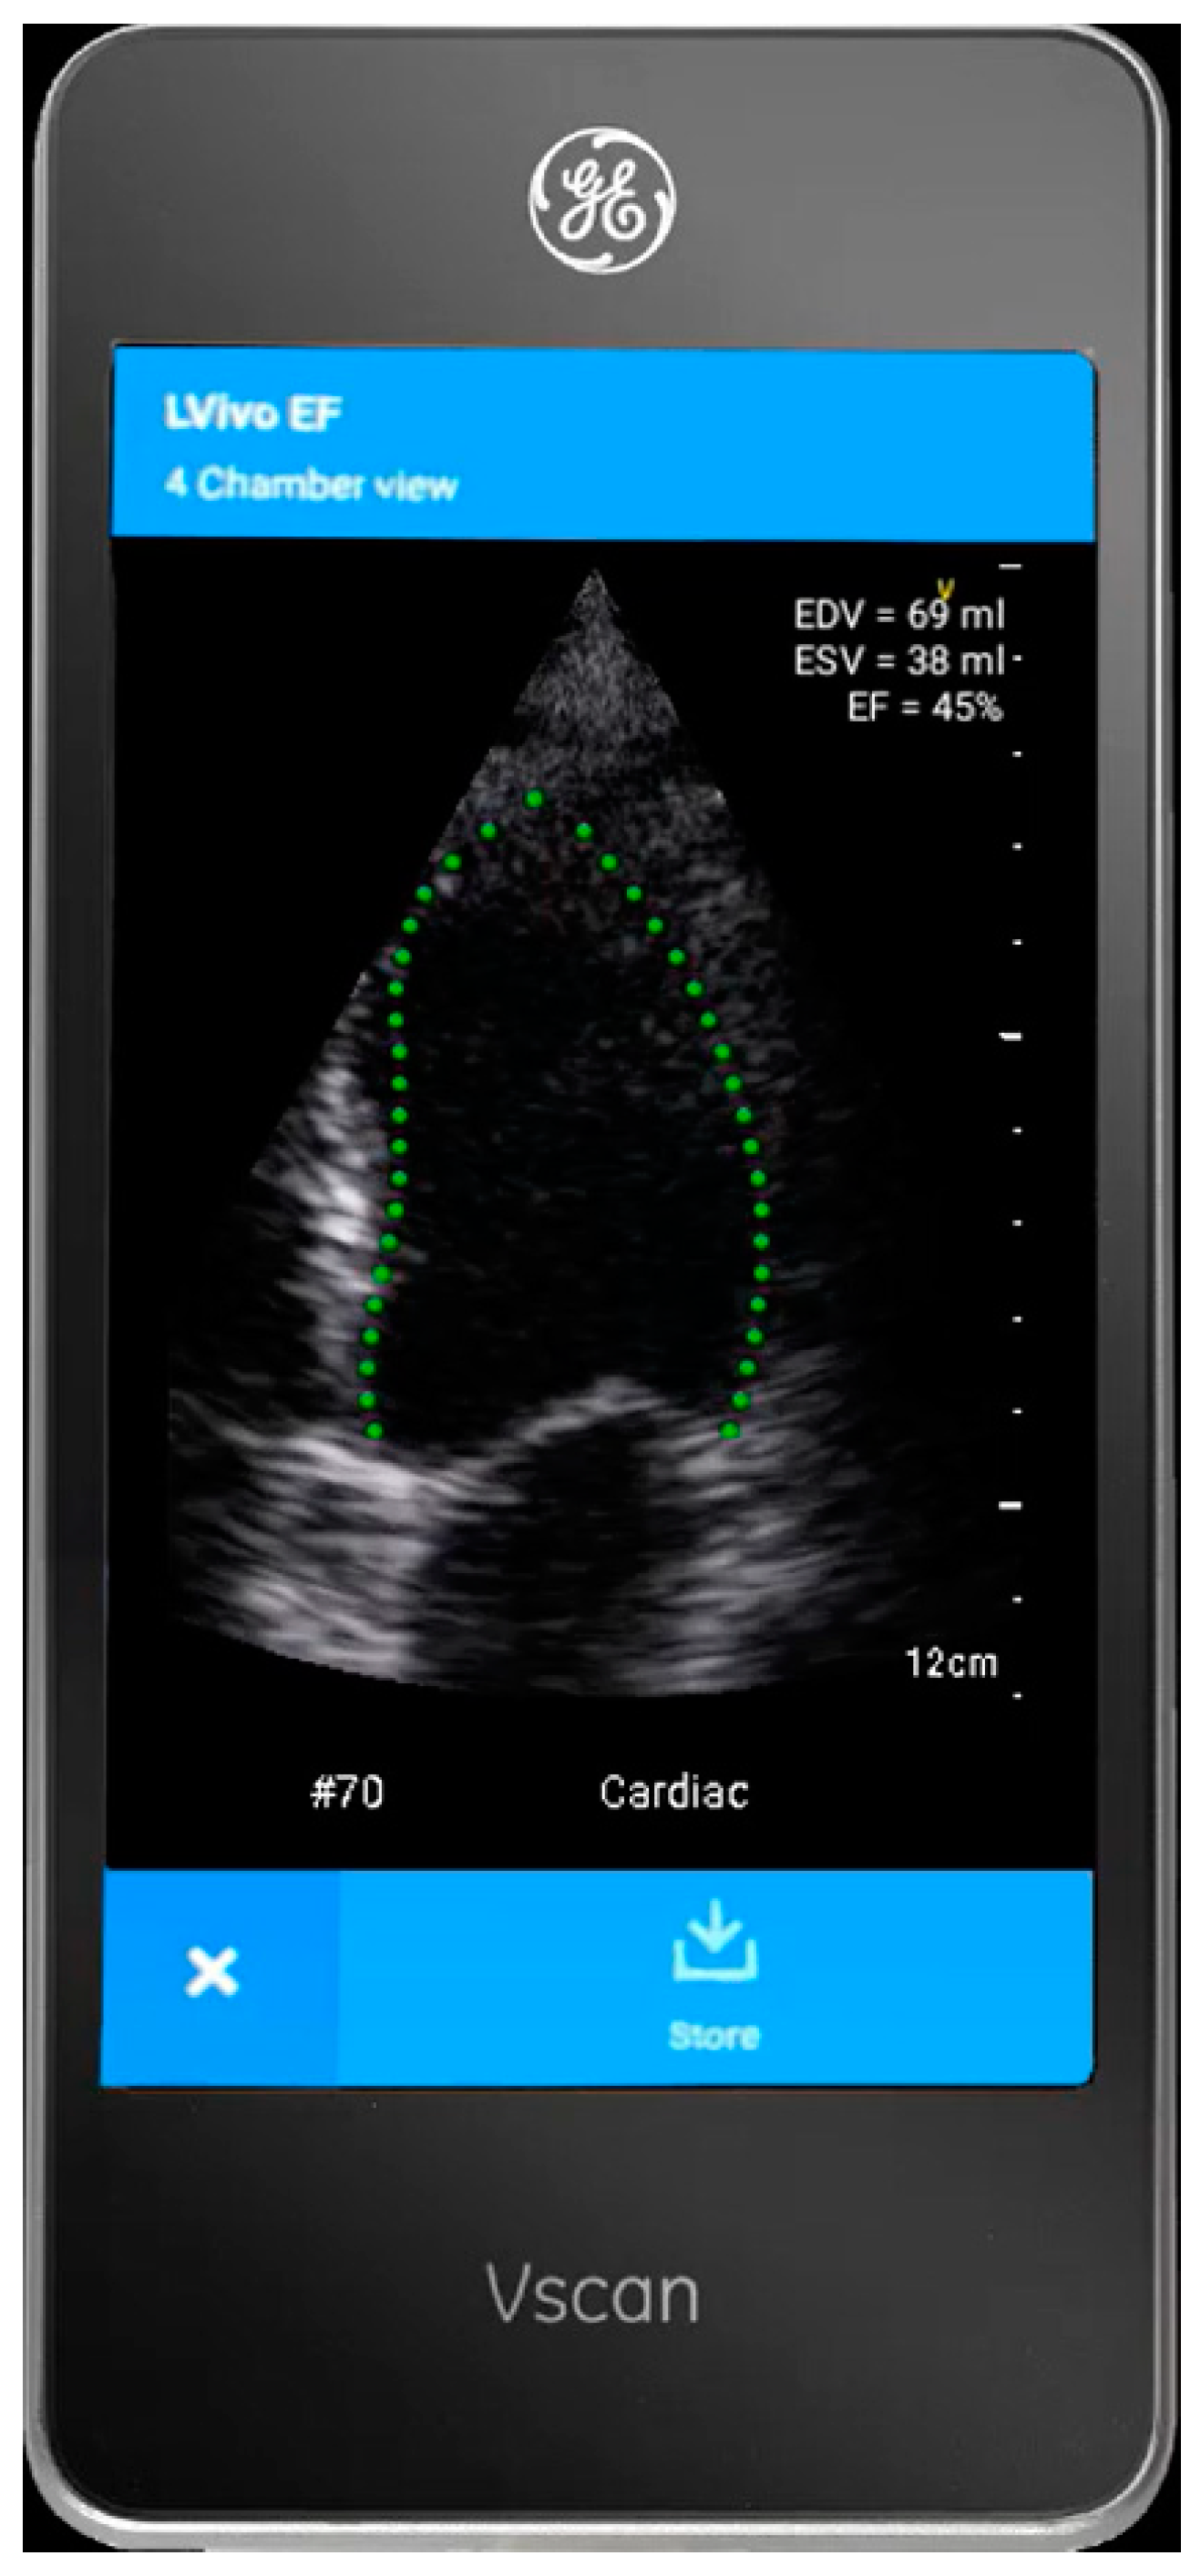

2.2. The AI-Based Tool